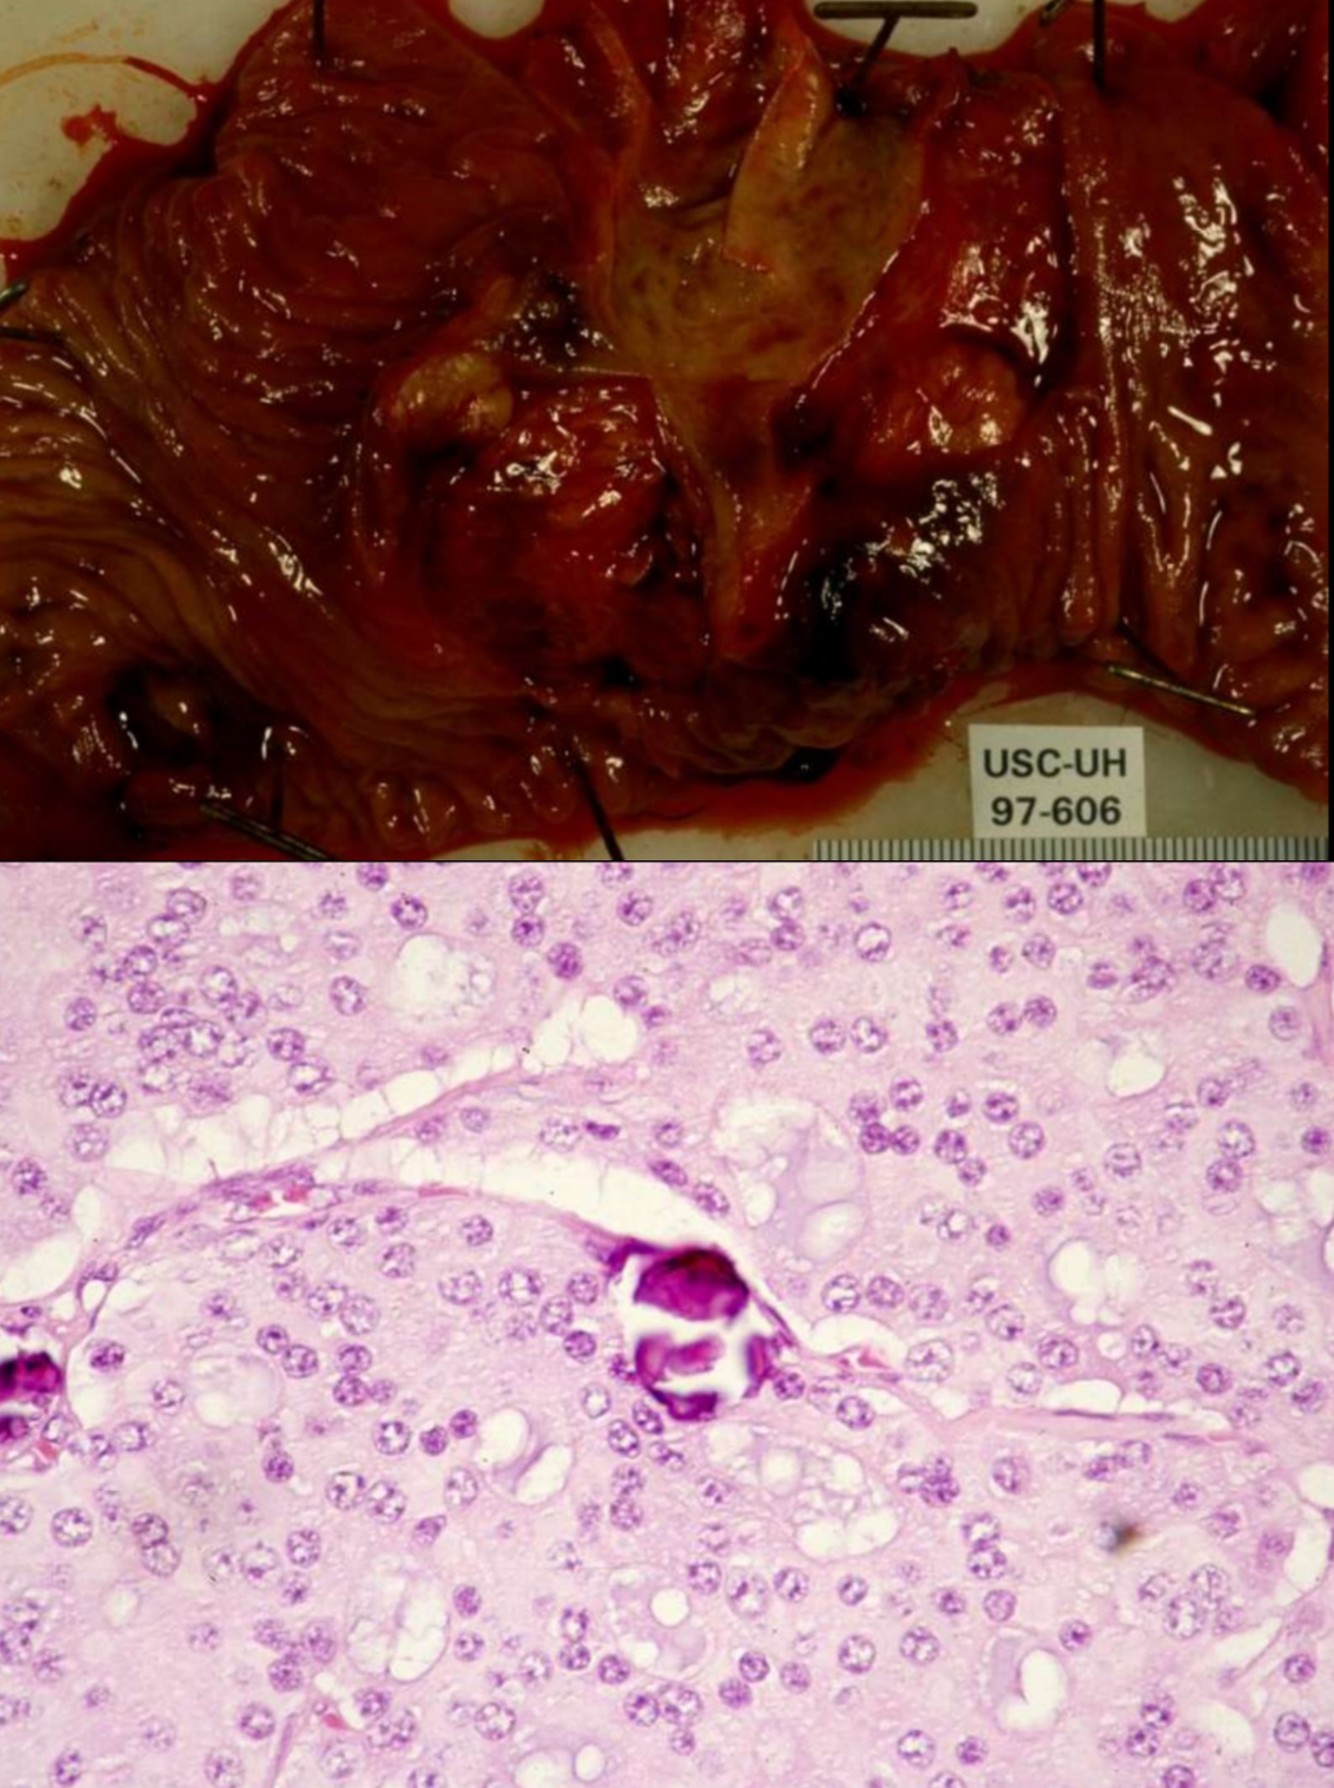

Infant of a diabetic mother

Dx in infant?

Increased risks?

Tx?